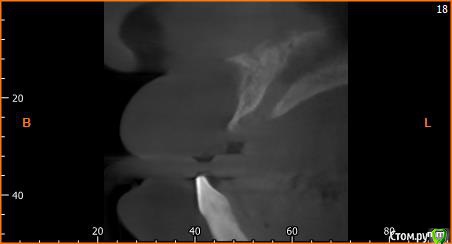

Собственно ситуация такая. Фронтальные зубы сверху были потеряны в результате серьезной травмы,  ! Фактически полное отсутствие костной ткани в области фронтальных зубов и по толщине и по высоте. Пациент ходит с чс протезом и хочет нечто несъемное.

Интересует как лучше это сделать при таких объемных дефектах.  Мои мысли первым этапом сосидж, потом 4 импланта. Но как быть с временным протезированием?

какой тут сосидж? Он для фронтального отдела не очень то годится.

Тут нужна вертикальная аугментация с каркасной мембраной.